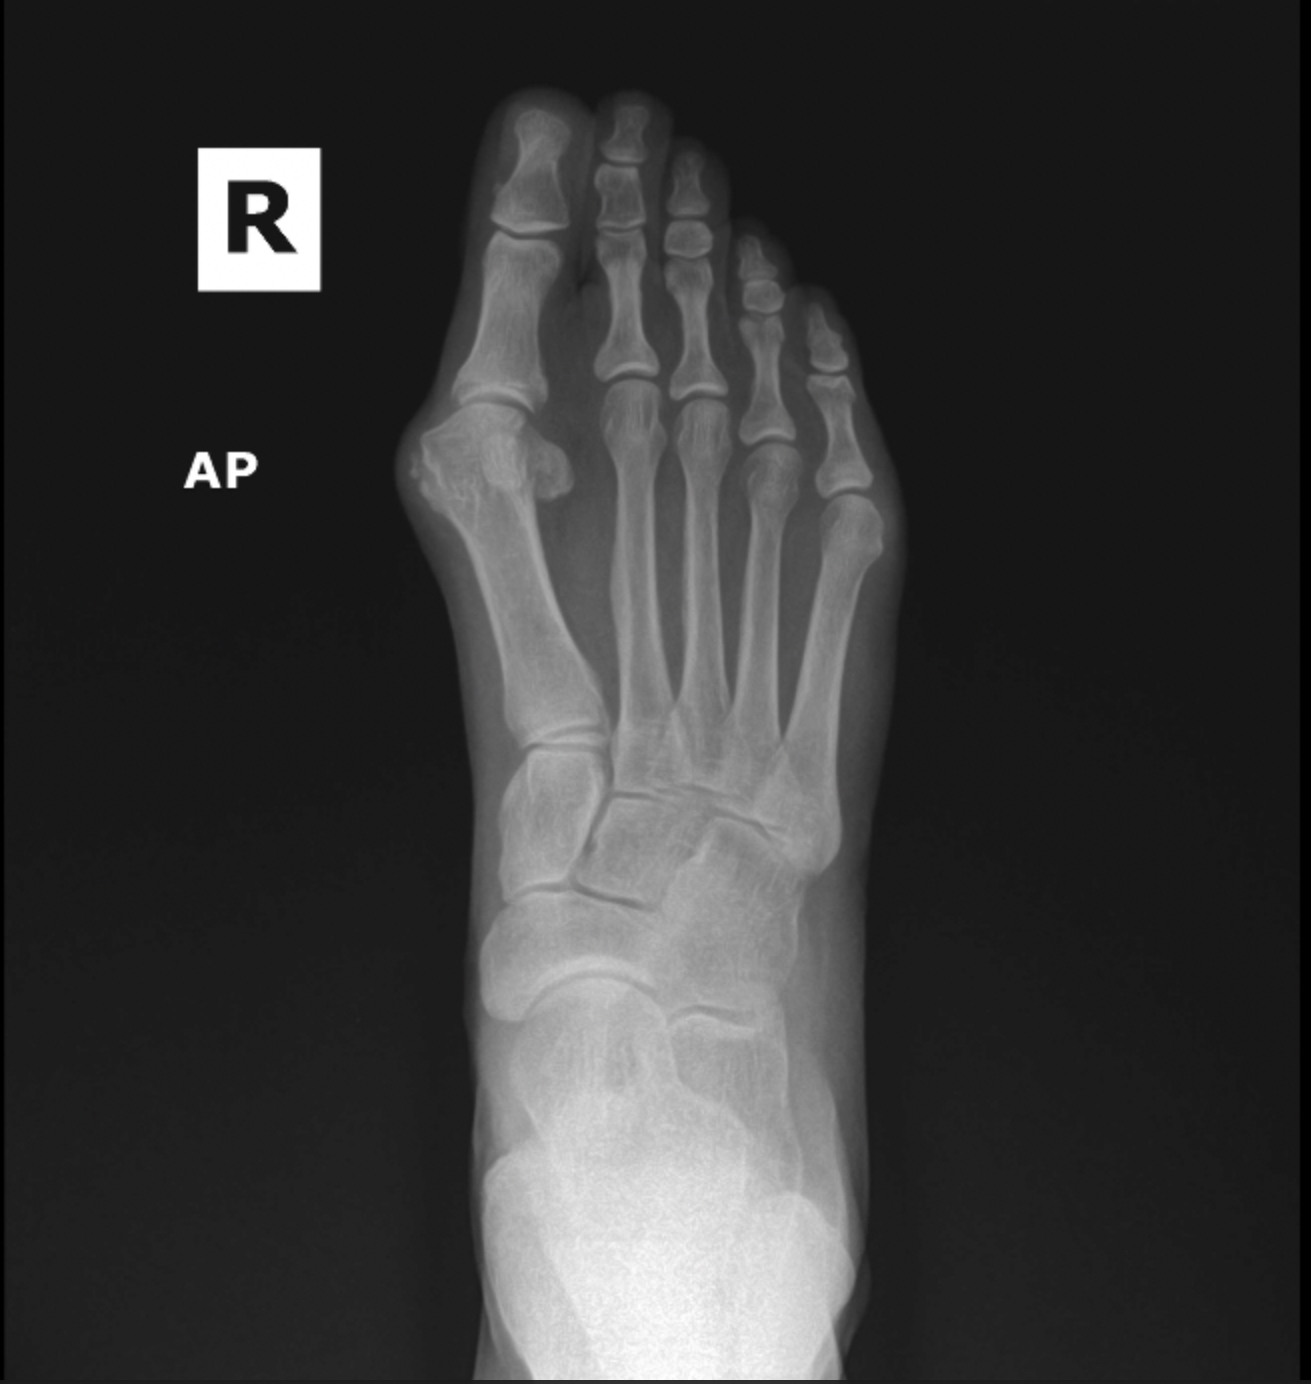

Arthritic flatfoot

Flatfoot deformity

Patient 1

Patient 2